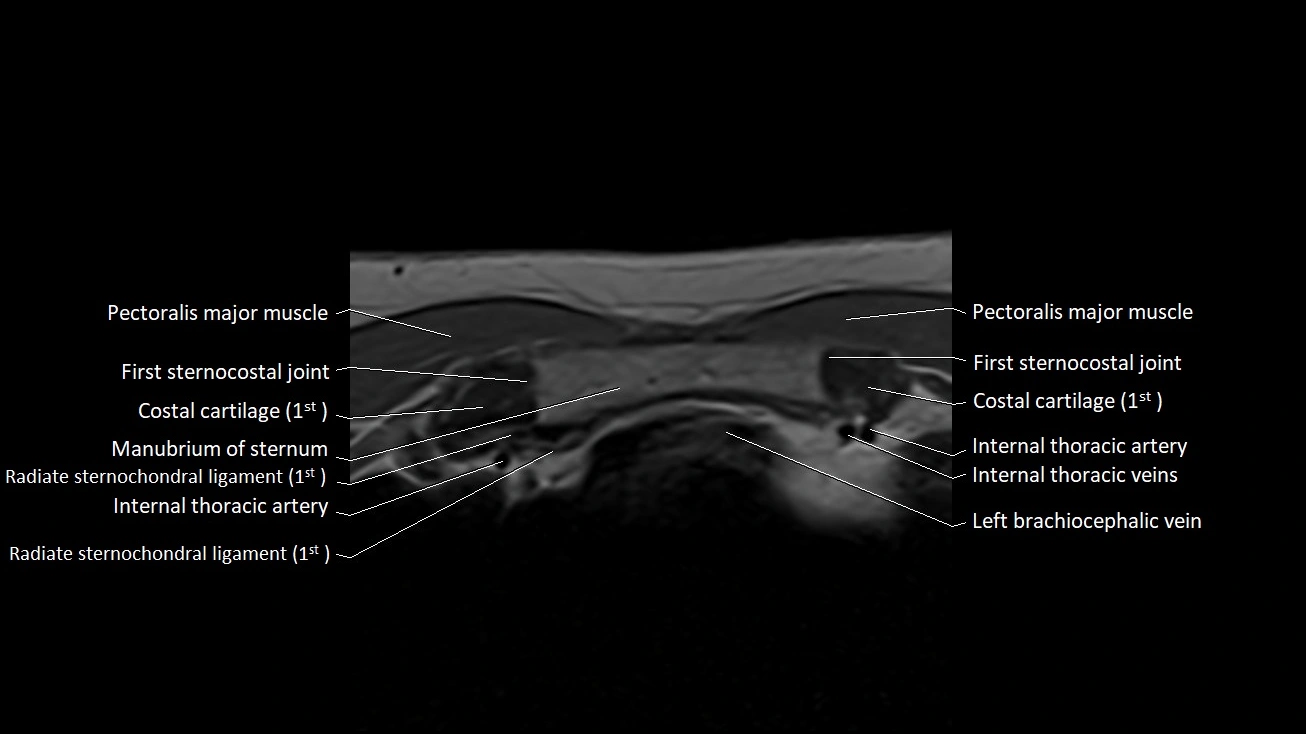

MRI images

image